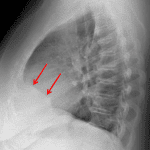

Age: 51

Sex: Female

Indication: Cough

Findings

- Clearly marginated hazy density along the anteromedial right lung base

Diagnosis

- Prominent pericardial fat

No evidence of acute cardiopulmonary disease.

Clearly marginated hazy density along the anteromedial right lung base likely represents prominent pericardial fat.